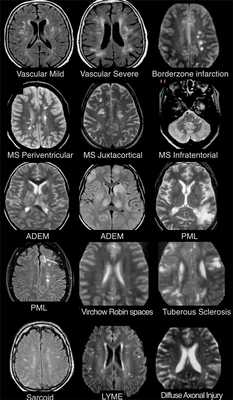

На изображениях определяются множественные точечные и «пятнистые» очаги (некоторые из них будут рассмотрены более детально).

Рассеянный склероз — хроническое аутоиммунное заболевание, при котором поражается миелиновая оболочка нервных волокон головного и спинного мозга, характеризующееся многоочаговостью поражения белого вещества центральной нервной системы, ремиттирующе-прогредиентным течением, вариабельностью неврологических симптомов и преимущественным поражением лиц молодого возраста (подробнее с диагностическими критериями указанного заболевания Вы можете ознакомится в статье «Современные критерии диагностики рассеянного склероза», опубликованной на нашем сайте).

- Главное отличие инфарктов (инсультов) этого типа — это предрасположенность к локализации очагов только в одном полушарии на границе крупных бассейнов кровоснабжения. На МР-томограмме представлен инфаркт в бассейне глубоких ветвей.

Острый диссеминированный энцефаломиелит (ОДЭМ)

- Основное отличие: появление мультифокальных участков в белом веществе и в области базальных ганглиев через 10-14 дней после перенесенной инфекции или вакцинации. Как при рассеянном склерозе, при ОДЭМ может поражаться спинной мозг, дугообразные волокна и мозолистое тело; в некоторых случаях очаги могут накапливать контраст. Отличием от РС считается тот момент, что они имеют большой размер и возникают преимущественно у молодых пациентов. Заболевание отличается монофазным течением

Саркоидоз головного мозга

- Распределение очаговых изменений при саркоидозе крайне напоминает таковое при рассеянном склерозе.

Прогрессирующая мультфокальная лейкоэнцефалопатия (ПМЛ)

- Демиелинизирующее заболевание, обусловленное вирусом Джона Каннигема у пациентов с иммунодефицитом. Ключевым признаком являются поражения белого вещества в области дугообразных волокон, не усиливающиеся при контрастировании, оказывающие объемное воздействие (в отличие от поражений, обусловленных ВИЧ или цитомегаловирусом). Патологические участки при ПМЛ могут быть односторонними, но чаще они возникают с обеих сторон и являются асимметричными.

- Для зон сосудистого характера типична глубокая локализация в белом веществе, отсутствие вовлечения мозолистого тела, а также юкставентрикулярных и юкстакортикальных участков.

ДИФФЕРЕНЦИАЛЬНАЯ ДИАГНОСТИКА МНОЖЕСТВЕННЫХ ОЧАГОВ, УСИЛИВАЮЩИХСЯ ПРИ КОНТРАСТИРОВАНИИ

На МР-томограммах продемонстрированы множественные патологические зоны, накапливающие контрастное веществ (некоторые из них описаны далее подробнее).

- Большинство васкулитов характеризуются возникновением точечных очаговых изменений, усиливающихся при контрастировании. Поражение сосудов головного мозга наблюдается при системной красной волчанке, паранеопластическом лимбическом энцефалите, б. Бехчета, сифилисе, гранулематозе Вегенера, б. Шегрена, а также при первичных ангиитах ЦНС.

- Характеризуются выраженным перифокальным отеком.

- Периферические инфаркты краевой зоны могут усиливаться при контрастировании на ранней стадии.